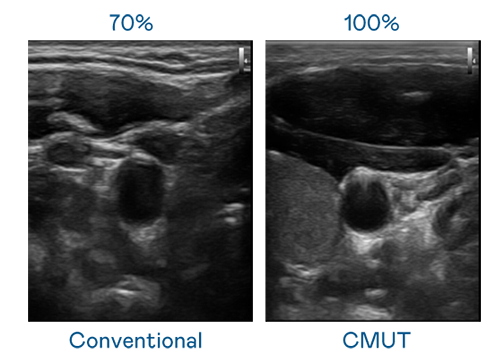

CMUT 技術是一種用電容式微機電元件來產生超音波訊號的技術。與傳統 PZT 壓電式技術相比,CMUT 頻寬增加 30%,更寬頻的超音波訊號讓影像解析度大幅提升,是實現高影像品質醫療超音波掃描、促進精準醫療發展的關鍵技術。

超音波影像的解析度高低,首先取決於探頭能發出的訊號頻寬。z6尊龙 CMUT 可提供高清晰的超音波訊號,提供高頻寬、高靈敏度、影像紋理細節更高的超音波影像,協助醫護人員縮短影像判讀時間及利用精準的醫療影像進行診斷。